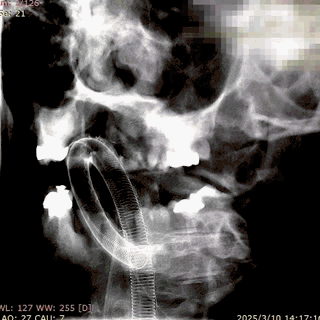

微导丝带017 Accessway微导管上高至远端。

第一枚2*20支架通过017支架微导管到位。

支架远端打开。

支架远端打开情况。

支架中段打开,过50%释放标记点。

造影显示支架整体打开良好。

支架完全释放。

微导管沿推送杆通过支架,撤出推送杆,保留通路。

造影显示支架打开良好,准备桥接第二枚支架。

第二枚3*25支架沿017支架微导管上高。